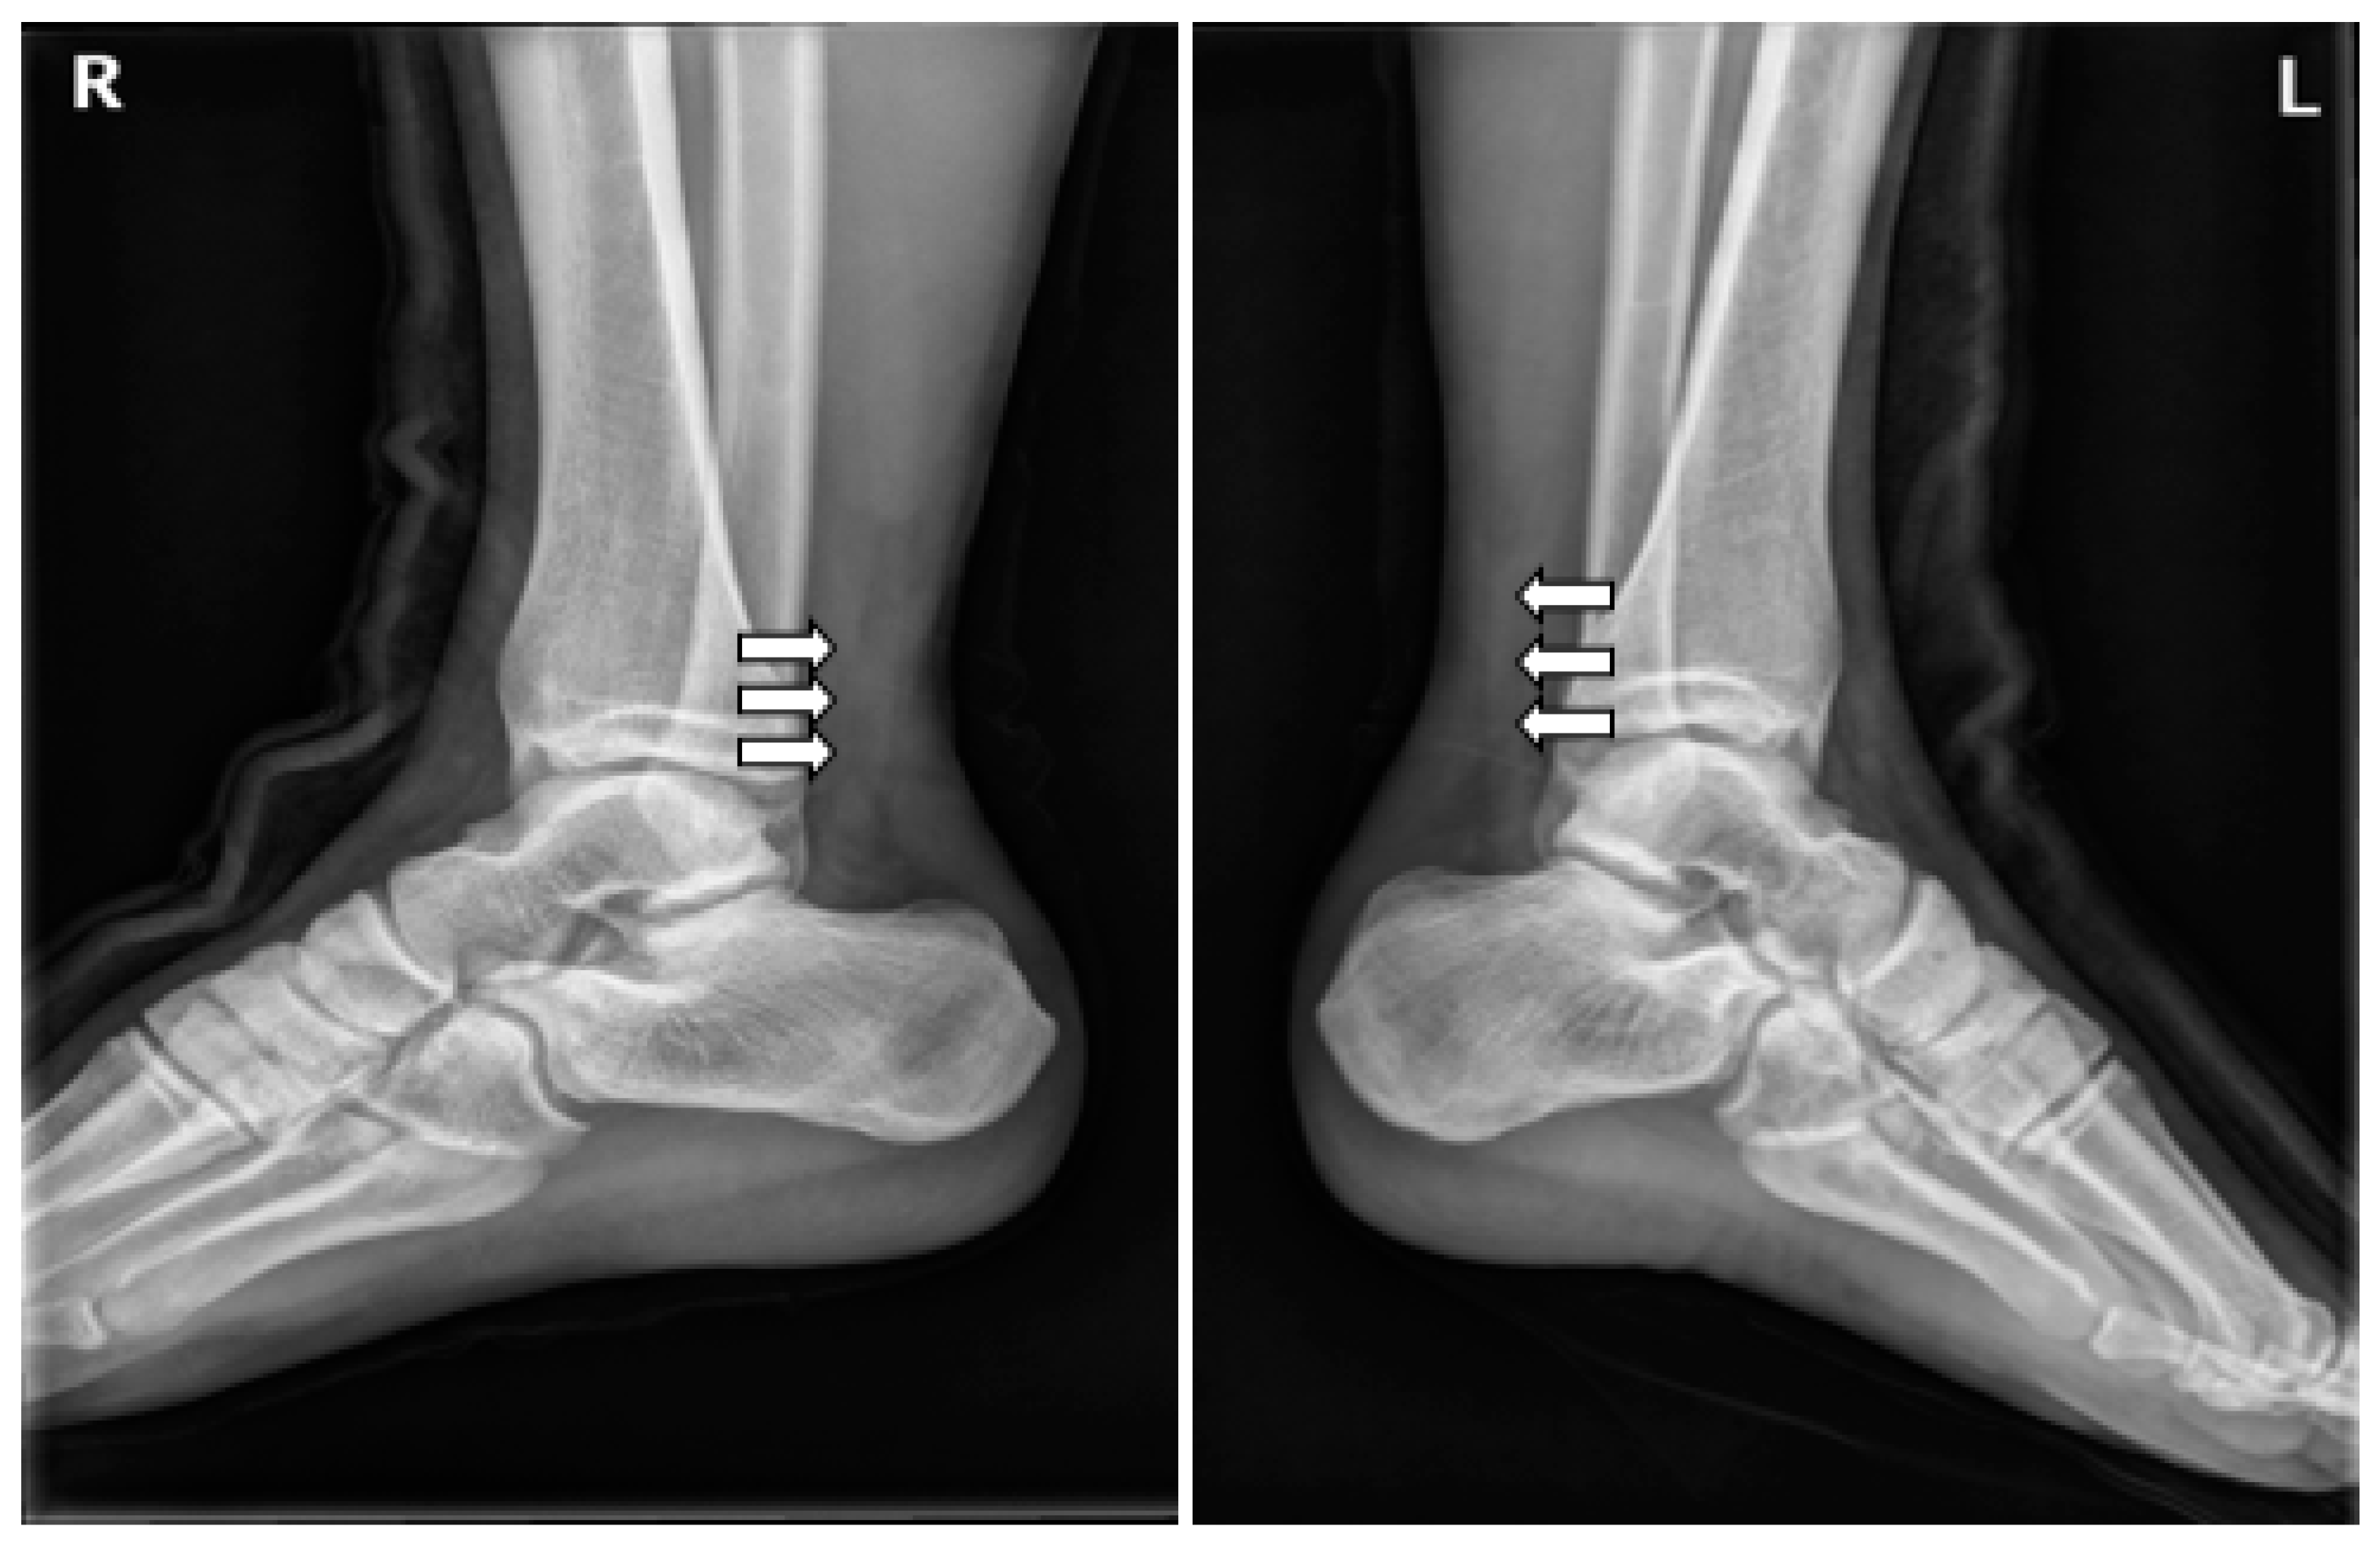

At the time of admission, the Thompson squeeze test was positive in both ankles, and digital exploration revealed dimpling 6 cm superior to the calcaneal tendon attachment site. Preoperative ankle radiographs showed no abnormality in the bone or surrounding soft tissue, other than the loss of Kager’s triangle (Figure 2). MRI confirmed the diagnosis of bilateral AT rupture (Figure 3).

Figure 2. Lateral conventional radiographs of both ankles following bilateral Achilles tendon rupture show marked thickening of the Achilles tendons, loss of the normal sharp anterior borders (white arrows), and effacement of the pre-Achilles/Kager’s fat pad.